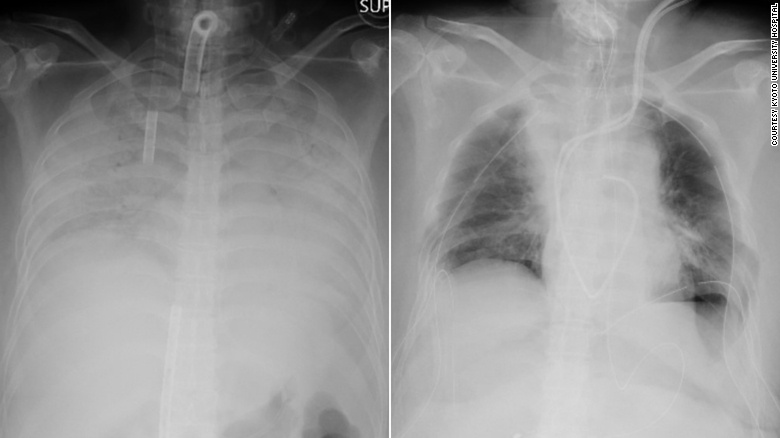

Hình ảnh X-quang trước và sau khi ghép phổi cho bệnh nhân. Vùng tối là khu vực mô phổi được cấy ghép. Ảnh: Bệnh viện Đại học Kyoto.

Trước đó, người phụ nữ ở Kansai, phía tây Nhật Bản, không có tiền sử bệnh tật, nhưng chức năng phổi của bà bị suy giảm nhanh chóng sau khi mắc Covid-19 vào cuối năm 2020. Căn bệnh khiến cả hai phổi của bà đều cứng và co lại, phá hủy hầu hết chức năng. Bà phải sử dụng máy thở hỗ trợ và cần ghép phổi để duy trì sự sống.

Người phụ nữ mắc Covid-19 bị tổn thương phổi nghiêm trọng nhập viện vào ngày 5/4 và được kết nối với thiết bị tim phổi nhân tạo (ECMO). Bà được ghép một phần phổi trái của chồng và một phần phổi phải của con trai 2 ngày sau đó.